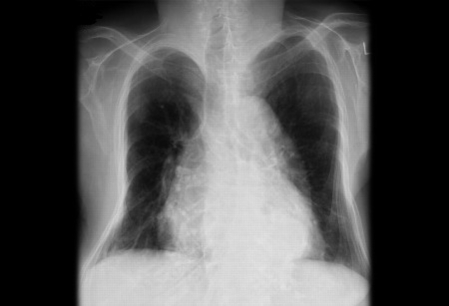

Radiografia torácica mostrando deformidade acentuada e perda de volume do tórax ósseo em um paciente com osteoporose

BMJ Case Reports 2009; doi:10.1136/bcr.07.2008.0359. Copyright ©BMJ publishing group 2010